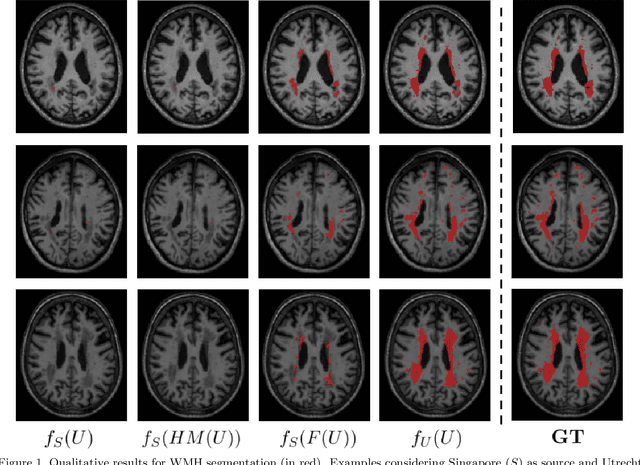

Automatic segmentation of white matter hyperintensities in magnetic resonance images is of paramount clinical and research importance. Quantification of these lesions serve as a predictor for risk of stroke, dementia and mortality. During the last years, convolutional neural networks (CNN) specifically tailored for biomedical image segmentation have outperformed all previous techniques in this task. However, they are extremely data-dependent, and maintain a good performance only when data distribution between training and test datasets remains unchanged. When such distribution changes but we still aim at performing the same task, we incur in a domain adaptation problem (e.g. using a different MR machine or different acquisition parameters for training and test data). In this work, we explore the use of cycle-consistent adversarial networks (CycleGAN) to perform unsupervised domain adaptation on multicenter MR images with brain lesions. We aim at learning a mapping function to transform volumetric MR images between domains, which are characterized by different medical centers and MR machines with varying brand, model and configuration parameters. Our experiments show that CycleGAN allows us to reduce the Jensen-Shannon divergence between MR domains, enabling automatic segmentation with CNN models on domains where no labeled data was available.